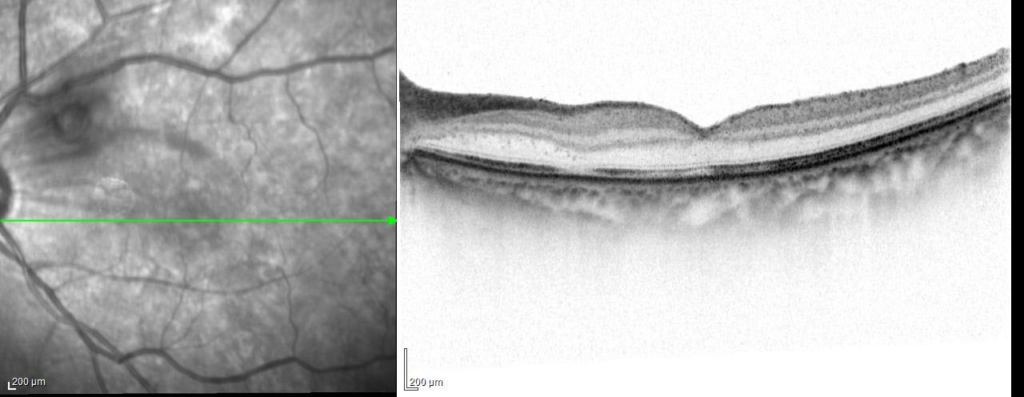

術後視力 左眼 0.15p(0.5×+1.50=c-1.50A90°)

硝子体手術、PVD作成し血種除去。